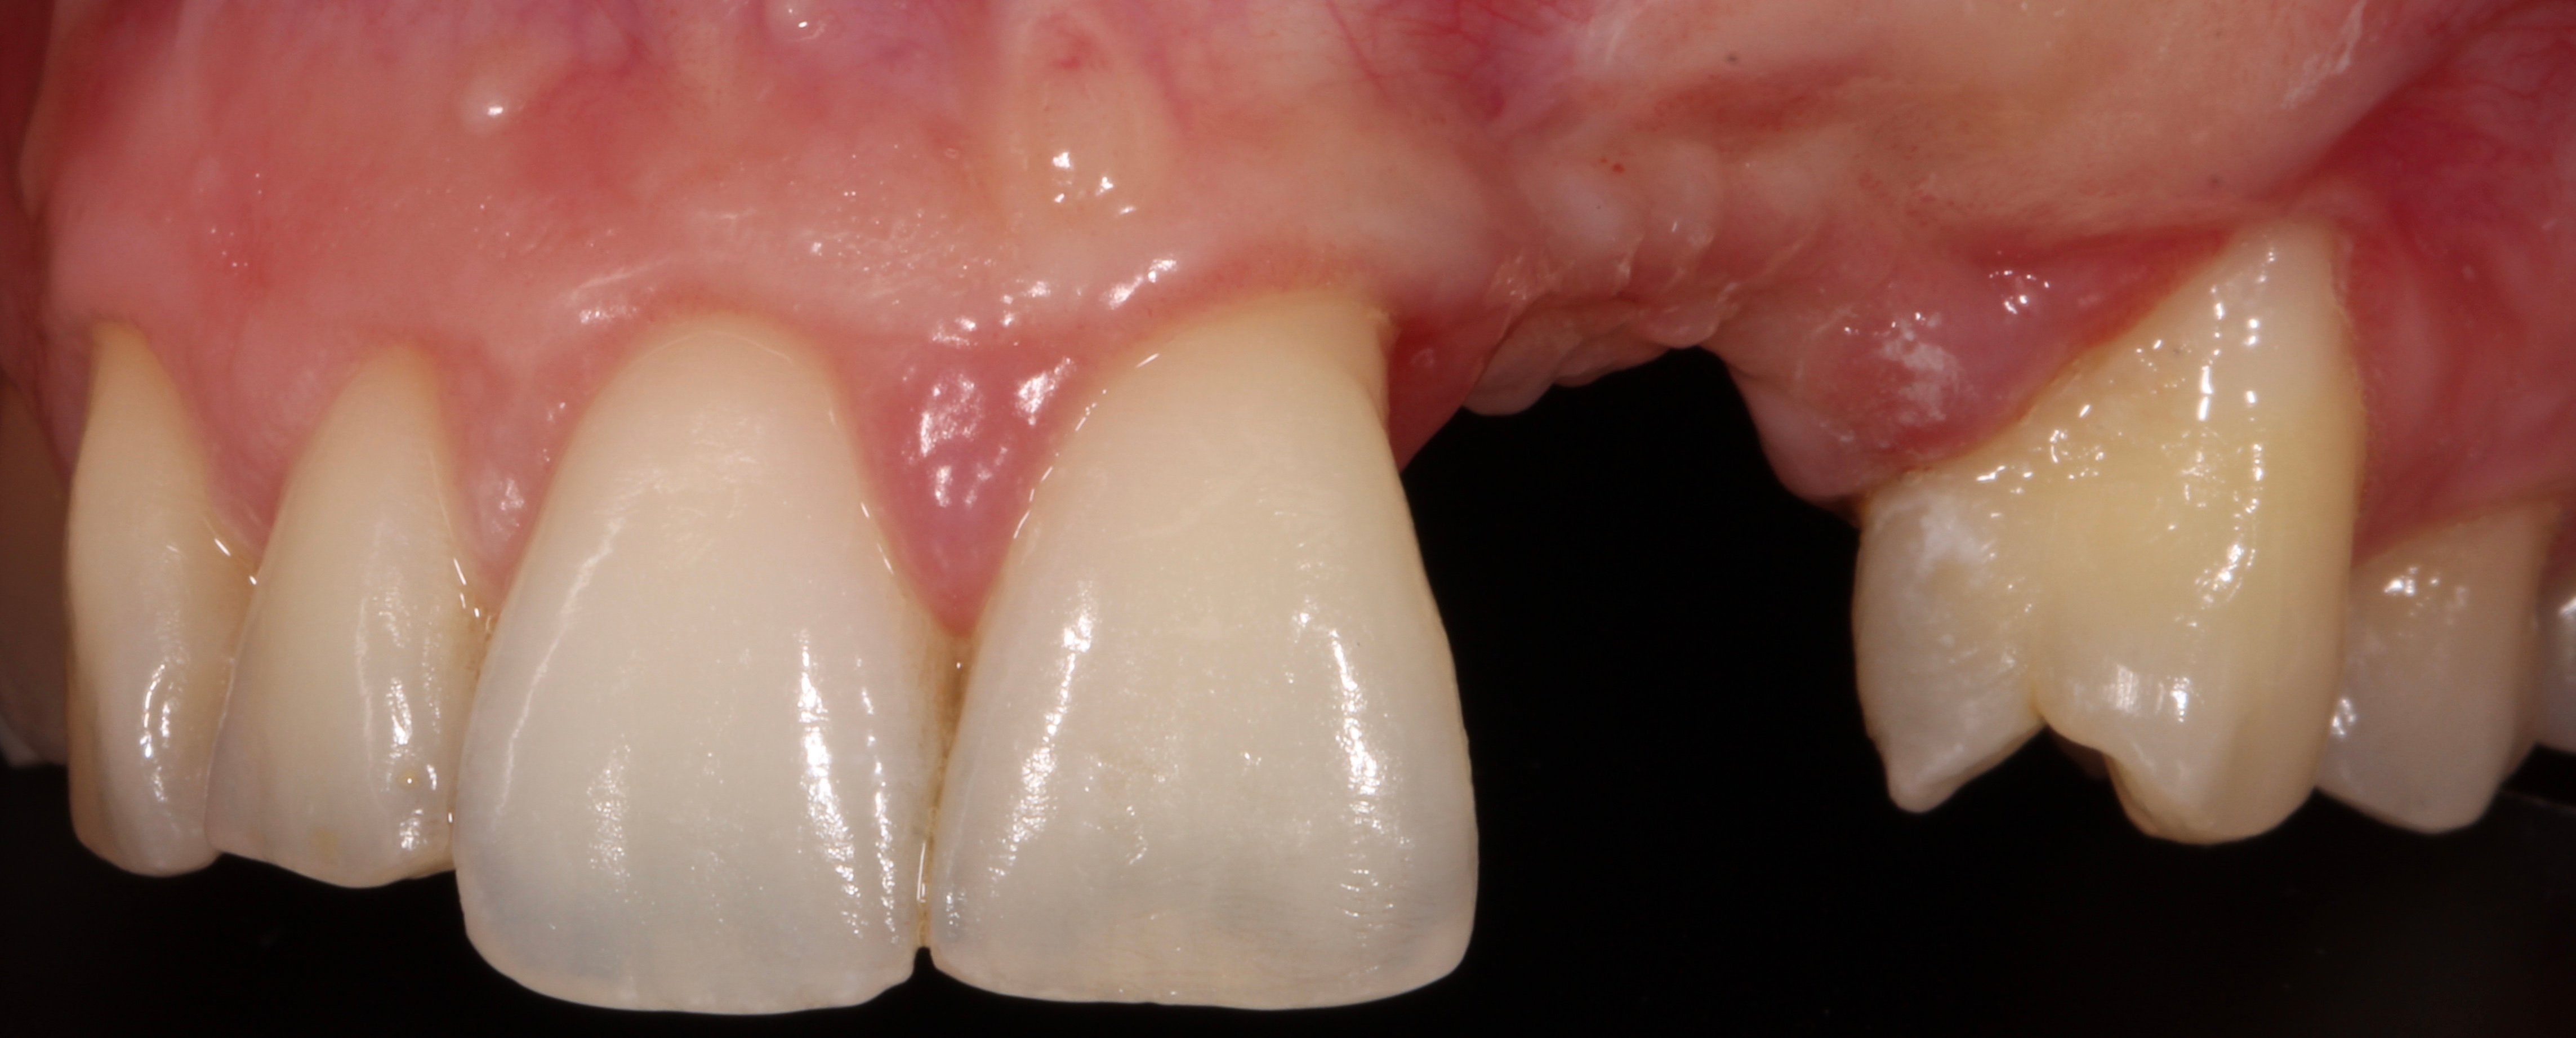

- 1 year later: Reentry and implant placement at 23 + connective tissue graft to solve the papilla loss at distal aspect of tooth 21.

- 2 months later: Free connective tissue to reposition the mucogingival line.